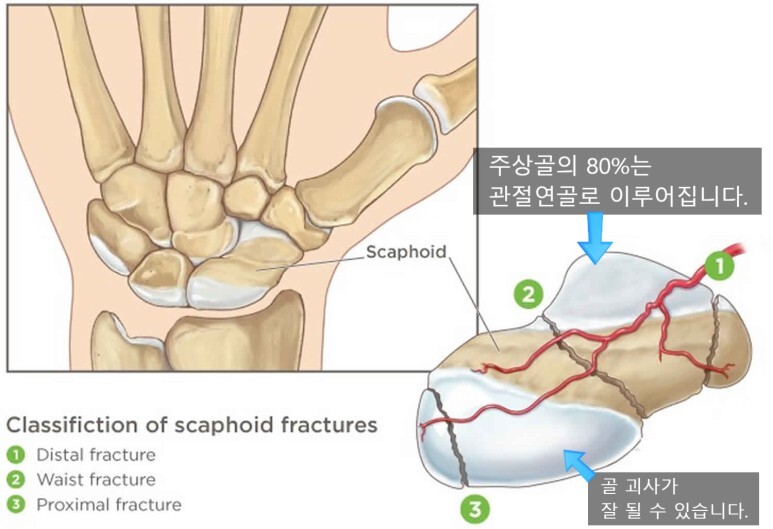

- 주상골은 손목 관절뼈 중 중요한 역할을 합니다. 그런데 골절이 된 이후에는 뼈가 잘 붙지않는 불유합이나, 뼈에 혈액순환이 잘 안되서 뼈가 녹아버리는 골괴사가 발생할 수 있습니다. 이렇게 쉽게 문제가 생기는 이유는 혈류가 적고, 골절 시 혈관손상으로 혈액공급에 문제가 쉽게 발생할 수 있기 때문입니다. 따라서 약간의 뼈의 어긋남이 있어도 뼈가 잘 붙지 않을 수 있습니다.

- 아래 그림에서 골괴사가 잘 되는 이유를 모식도로 잘 설명했습니다. 혈액이 한쪽에서면 공급이되기때문에 골절이 되면 골절된 끝부분의 혈액공급이 잘 안될 수 있기 때문입니다.

2. 주상골 골절의 분류

- 주상골 골절은 골절의 위치에 따라 대략적으로 근위부, 요부(허리, 중간), 원위부 골절로 나누며, 그 치료 방법과 예후가 달라지게됩니다.

- 근위부(손목에 가까운 부분) : 20~25%, 혈류가 끝까지 잘 가지 않을 수 있어 예후가 좋지 않습니다.

- 요부(주상골 중간) : 60%, 2달정도 CAST

- 원위부(손목에서 먼 부분) : 10~20%, 혈류가 가까워서 예후가 좋습니다.